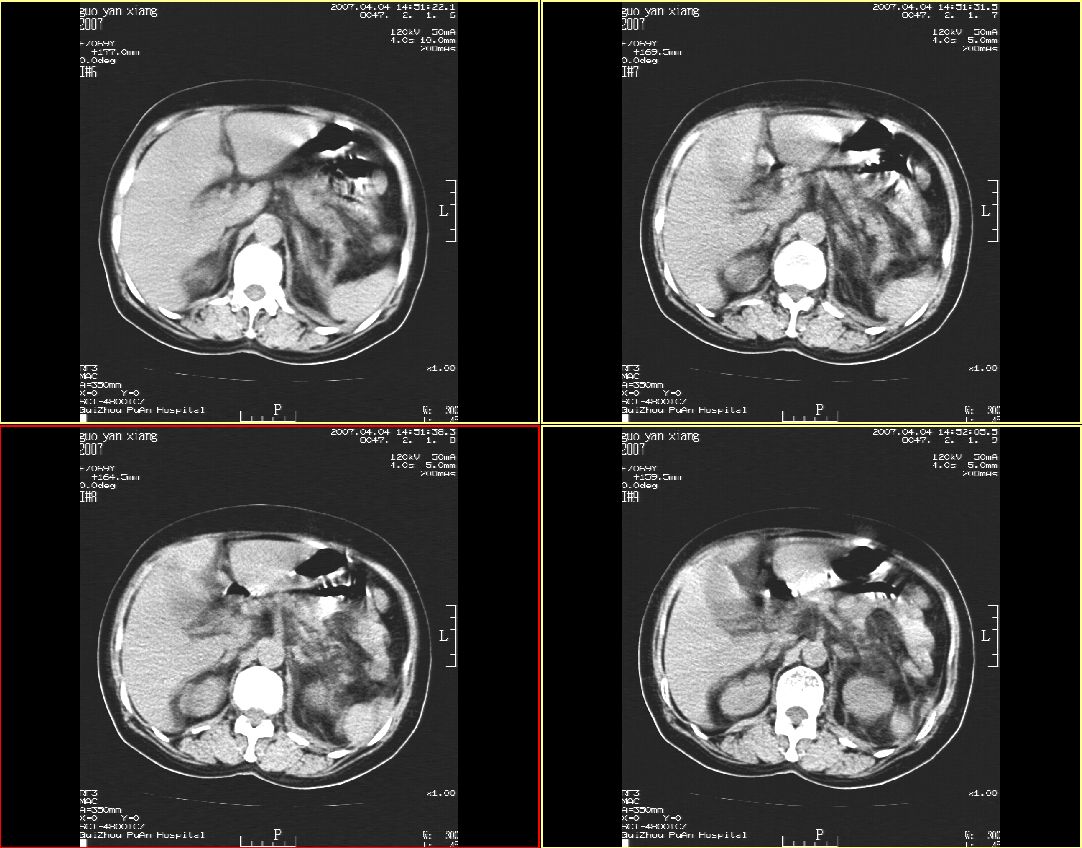

女性,59岁,腰痛,腹痛3天,未见肉眼血尿

左肾体弥漫性增大,肾周脂肪间囊密度增高,侧锥筋膜明显增厚,肾盂内见高密度影,左输尿管隐约可见,密度似较高,病程短,考虑:左肾急性肾盂肾炎,左肾盂内积血。不知临床还有没有其它相关体征及实验室检查?

肾周筋膜是增厚,肾盂内可见高密度影,但肾盂下部近输尿管处还是可见结石影。

左肾体弥漫性增大,肾周脂肪间囊密度增高,侧锥筋膜明显增厚,肾盂内见高密度影,左输尿管隐约可见,密度似较高,病程短,考虑:左肾急性肾盂肾炎,左肾盂内积血。腹膜炎。不知临床还有没有其它相关体征及实验室检查

左肾弥漫性增大,肾盂内见略高密度影,肾盂无明显扩张,肾实质密度均匀,肾周脂肪间囊密度增高,侧锥筋膜明显增厚,病程短,考虑:左肾急性肾盂肾炎,肾周感染,左肾盂内积血。建议完善相关检查或抗炎治疗后复查。